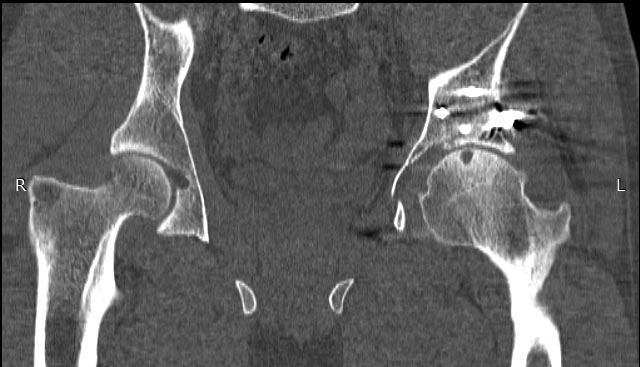

Мужчина 32 года, беспокоят боли в левом тазобедренном суставе, преимущественно в задних отделах при отведении ноги, иногда боли в паху с иррадиацией по внутренней поверхности до колена.

Травма в 2015 году. Водитель, попал в ДТП. Первично повреждение печени, перелом локтевой кости слева. Перелом задней колонный и задней стены левой вертлужной впадины. По экстренным показаниям выполнялась лапаротомия. Синтез задней колонны и задней стены через 13 дней через доступ Кохера-Лангенбека. Гладкий послеоперационный период. Выписан на амбулаторное лечение через 15 дней после операции. После выписки к нам не обращался, так как является жителем другого региона. Обратился через 2,5 года с жалобами на боли в области левого тазобедренного сустава.

На РКТ таза - перелом сросся. Отмечается кисты в области верхнего полюса головки бедра. Пластина фиксирующая задний край соприкасается с задними отделами головки бедра (видимо произошел частичный лизис костного края).